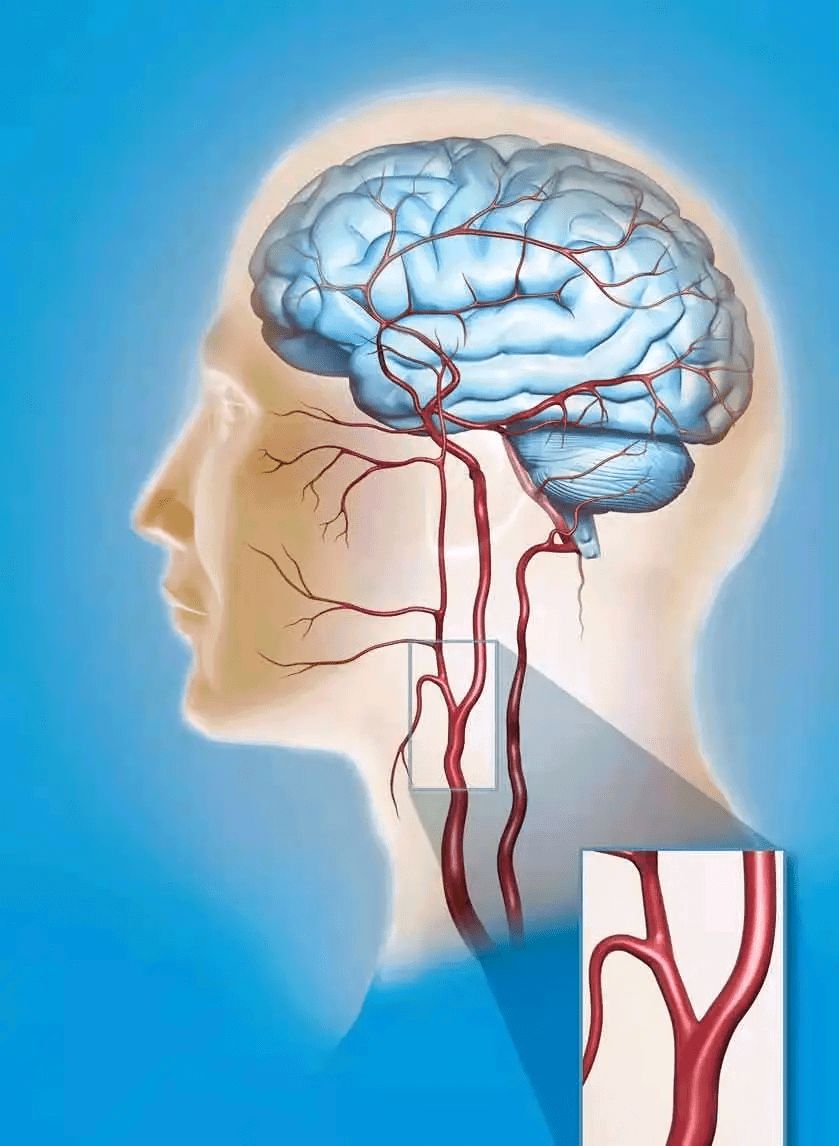

很多人做颈动脉超声会发现有颈动脉粥样斑块。那什么是颈动脉斑块呢?如何预防颈动脉斑块脱落呢?

颈动脉从结构上分为内膜,中膜,外膜,三层膜,颈动脉受损时从动脉内膜开始。比如,长期的高血压、高血糖使细胞受损,血管内皮上出现小的破口,血液中的低密度脂蛋白大量的聚集,大量的巨噬细胞就来吞噬这些物质,这些吞噬细胞受不了发生坏死。在局部形成脂质团块,形成了斑块,斑块经过一段时间形成包膜,又叫纤维帽,纤维帽厚度和结实程度决定斑块的稳定性。

需要通过颈动脉超声来测定颈动脉中膜的厚度来区分斑块的性质。

正常颈动脉内膜中层厚度应该小于1毫米,内膜增厚是1毫米到1.2毫米,大于1.2毫米可诊断为斑块形成。

高血压、高血糖的作用下可以使斑块破裂,一旦破裂,血液中起凝固作用的血小板就聚集在一起形成血栓,血栓可以从斑块上脱落,随着血液到处流动,堵塞血管,发生心梗、脑梗等。所以长的斑块为血栓发生创造了条件,是发生心脑血管疾病的高危因素。